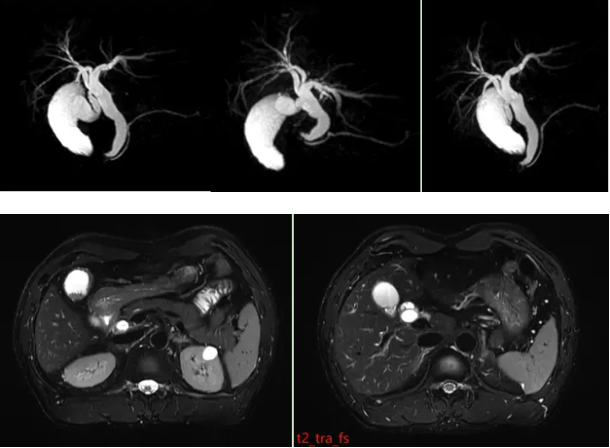

原理:MRCP(磁共振胰胆管水成像)利用水在磁共振重T2WI序列中呈高信号的特点,清晰显示胆汁充盈的胆管和胰管结构。

胆囊多发结石:图像显示胆囊内多个结节状短T2信号(结石在MRI中呈低信号暗影)。

胆总管扩张:胆总管直径增宽(正常值≤8mm),提示可能存在结石梗阻或炎症狭窄。

胆囊炎:胆囊壁增厚或周围渗出等间接征象。